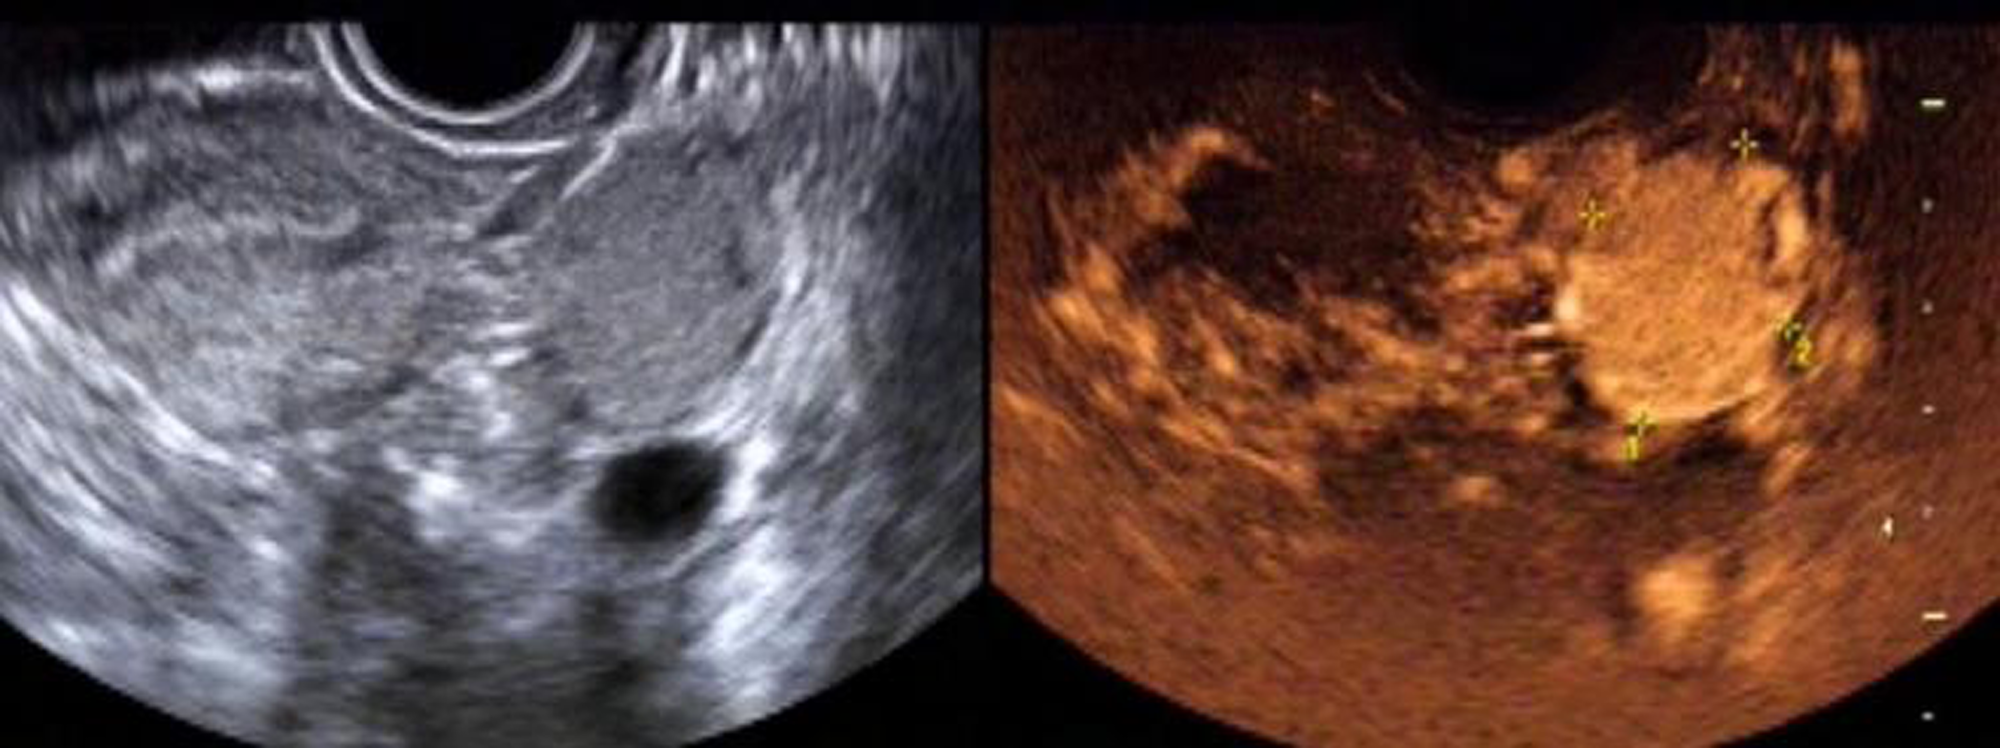

The sensitivity, specificity, positive predictive value, negative predictive value and accuracy of two-dimensional ultrasound combined with contrast-enhanced ultrasound in the diagnosis of ovarian cancer were high, 95.16%(59/62), 86.84%(33/38), 92.19%(59/64), 91.67%(33/36) and 92.00%(92/100), respectively. As shown in Table 2. The image of a typical case can be seen in Figure 5.

Figure 5

Female patient, 26 years old. Two-dimensional transvaginal ultrasound showed a round hypoecho in the left ovary, measuring about 3.5 cm × 2.4 cm × 3.1 cm, clear and regular in boundary, and uneven in internal echo. On CDFI, blood flow signals in the form of dots and strips were observed. According to contrast-enhanced ultrasound, the lesion in the left ovary was enhanced slightly earlier than that in the myometrium, and rapidly and integrally enhanced from multiple points in the center to the periphery, with the enhancement degree significantly higher than that in the myometrium. The lesion was cleared away from the center to the periphery, presenting as “fast forward and slow reverse”. The capsule echo appeared to be seen from the lesion in the early filling and late resolution.